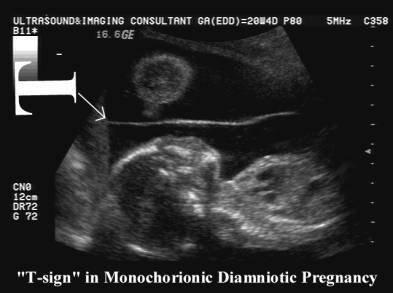

Qual sinal USG de gestação MONOcoriônica?

Sinal do T